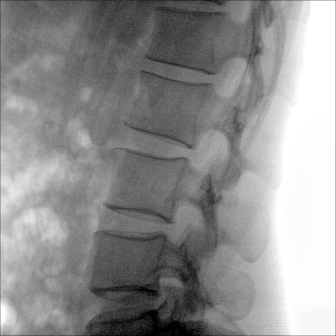

臨床適用科室:骨科、普通外科、矯形外科、創(chuàng)傷外科、泌尿外科、脊柱外科、疼痛外科、消化科、婦科等科室。

大尺寸動態(tài)平板探測器,高DQE、低噪聲、圖像清晰。采用多分辨率圖像增強(qiáng)處理技術(shù),不同部位不同圖像處理算法,滿足客戶多樣化的需求。